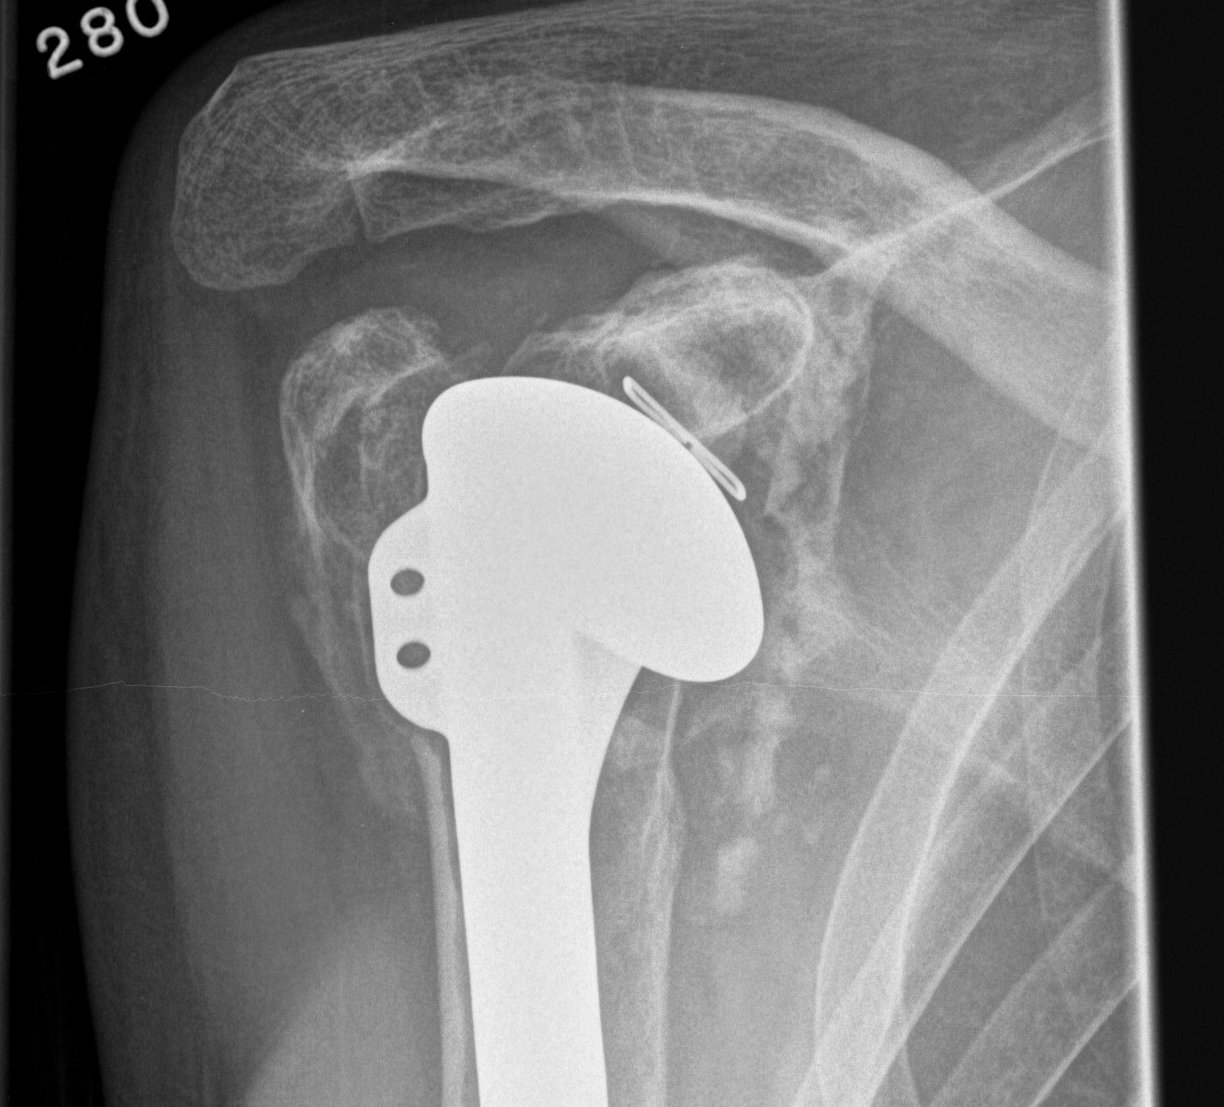

Superior rotator cuff failure

Cause

Humerus overstuffing

Glenoid superior tilting

Failed rotator cuff repair

aTSA overstuffing

Prevention

Must ensure don't leave humeral head proud

- restore Shenton's line

Issue

Results in eccentric loading of the superior aspect of glenoid component & loosening

- "rocking horse glenoid"

Diagnosis

Superior migration of humeral head on xray

Shoulder Hemiarthroplasty Rotator Cuff FailureTSR Superior EscapeaTSA failed cuffTSR Failed Rotator CUff

Incidence

Young et al. JBJS Am 2012

- 5 year follow up of 518 aTSA

- incidence of cuff failure of 17%

Options

Overstuffed aTSARevision to revTSA

Revision to reverse TSA